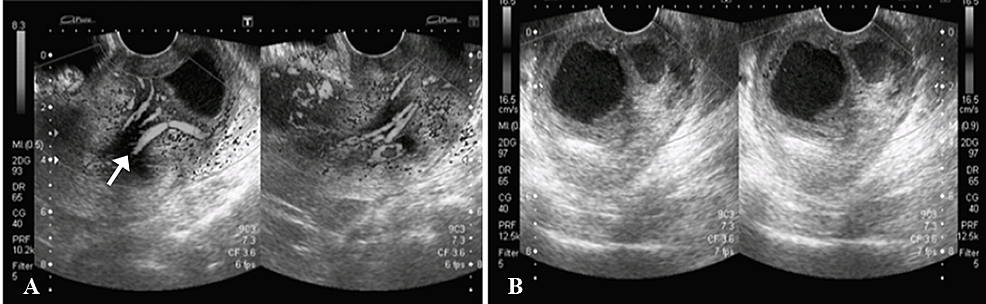

A 44-year-old previously healthy woman presented to the emergency department complaining of urinary retention. Transabdominal (Figure 1) and transvaginal (Figure 2) ultrasound showed a heterogeneous area measuring 53 x 27 mm in the superior one-third of vagina with evidence of cystic spaces containing internal echoes. Significant vascularity was seen in the lower endometrium and cervix which was extending into this heterogeneous area. The sonographic findings were concluded as a pedunculated endometrial polyp or prolapsed fibroid with cystic degeneration.